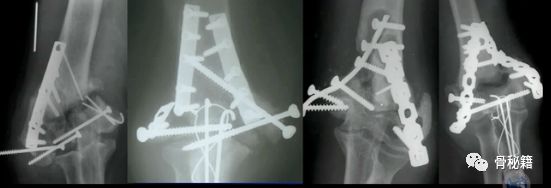

看看这些失败的case,肱骨远端不简单!

【骨折的复位和固定】

早期的AO技术

AO最早是90-90度钢板的派系,与平型钢板打的火热,后来没打过

1.钢板的形态没有特殊特定的,需要塑性预弯尤其在控制远端的骨折块的时候,钢板和螺钉的角度都必须十分讲究2. 对于滑车的固定只能应用最远端的拉力螺钉,与钢板不能连接3.这种固定在肱骨髁之间无法完成较好的骨折块之前的加压固定

所以对于这样固定的患者就面临一个问题,如果敢早期锻炼,就可能愈合不良,如果石膏固定时间长的话,肘关节就会僵硬

基于应用AO技术的话,固定要点1.一定要将钢板尽量往远端放,把远端骨块固定好2.髁间的固定一定要坚强,加压!3.尽量的坚强固定4.固定基础下早期功能锻炼